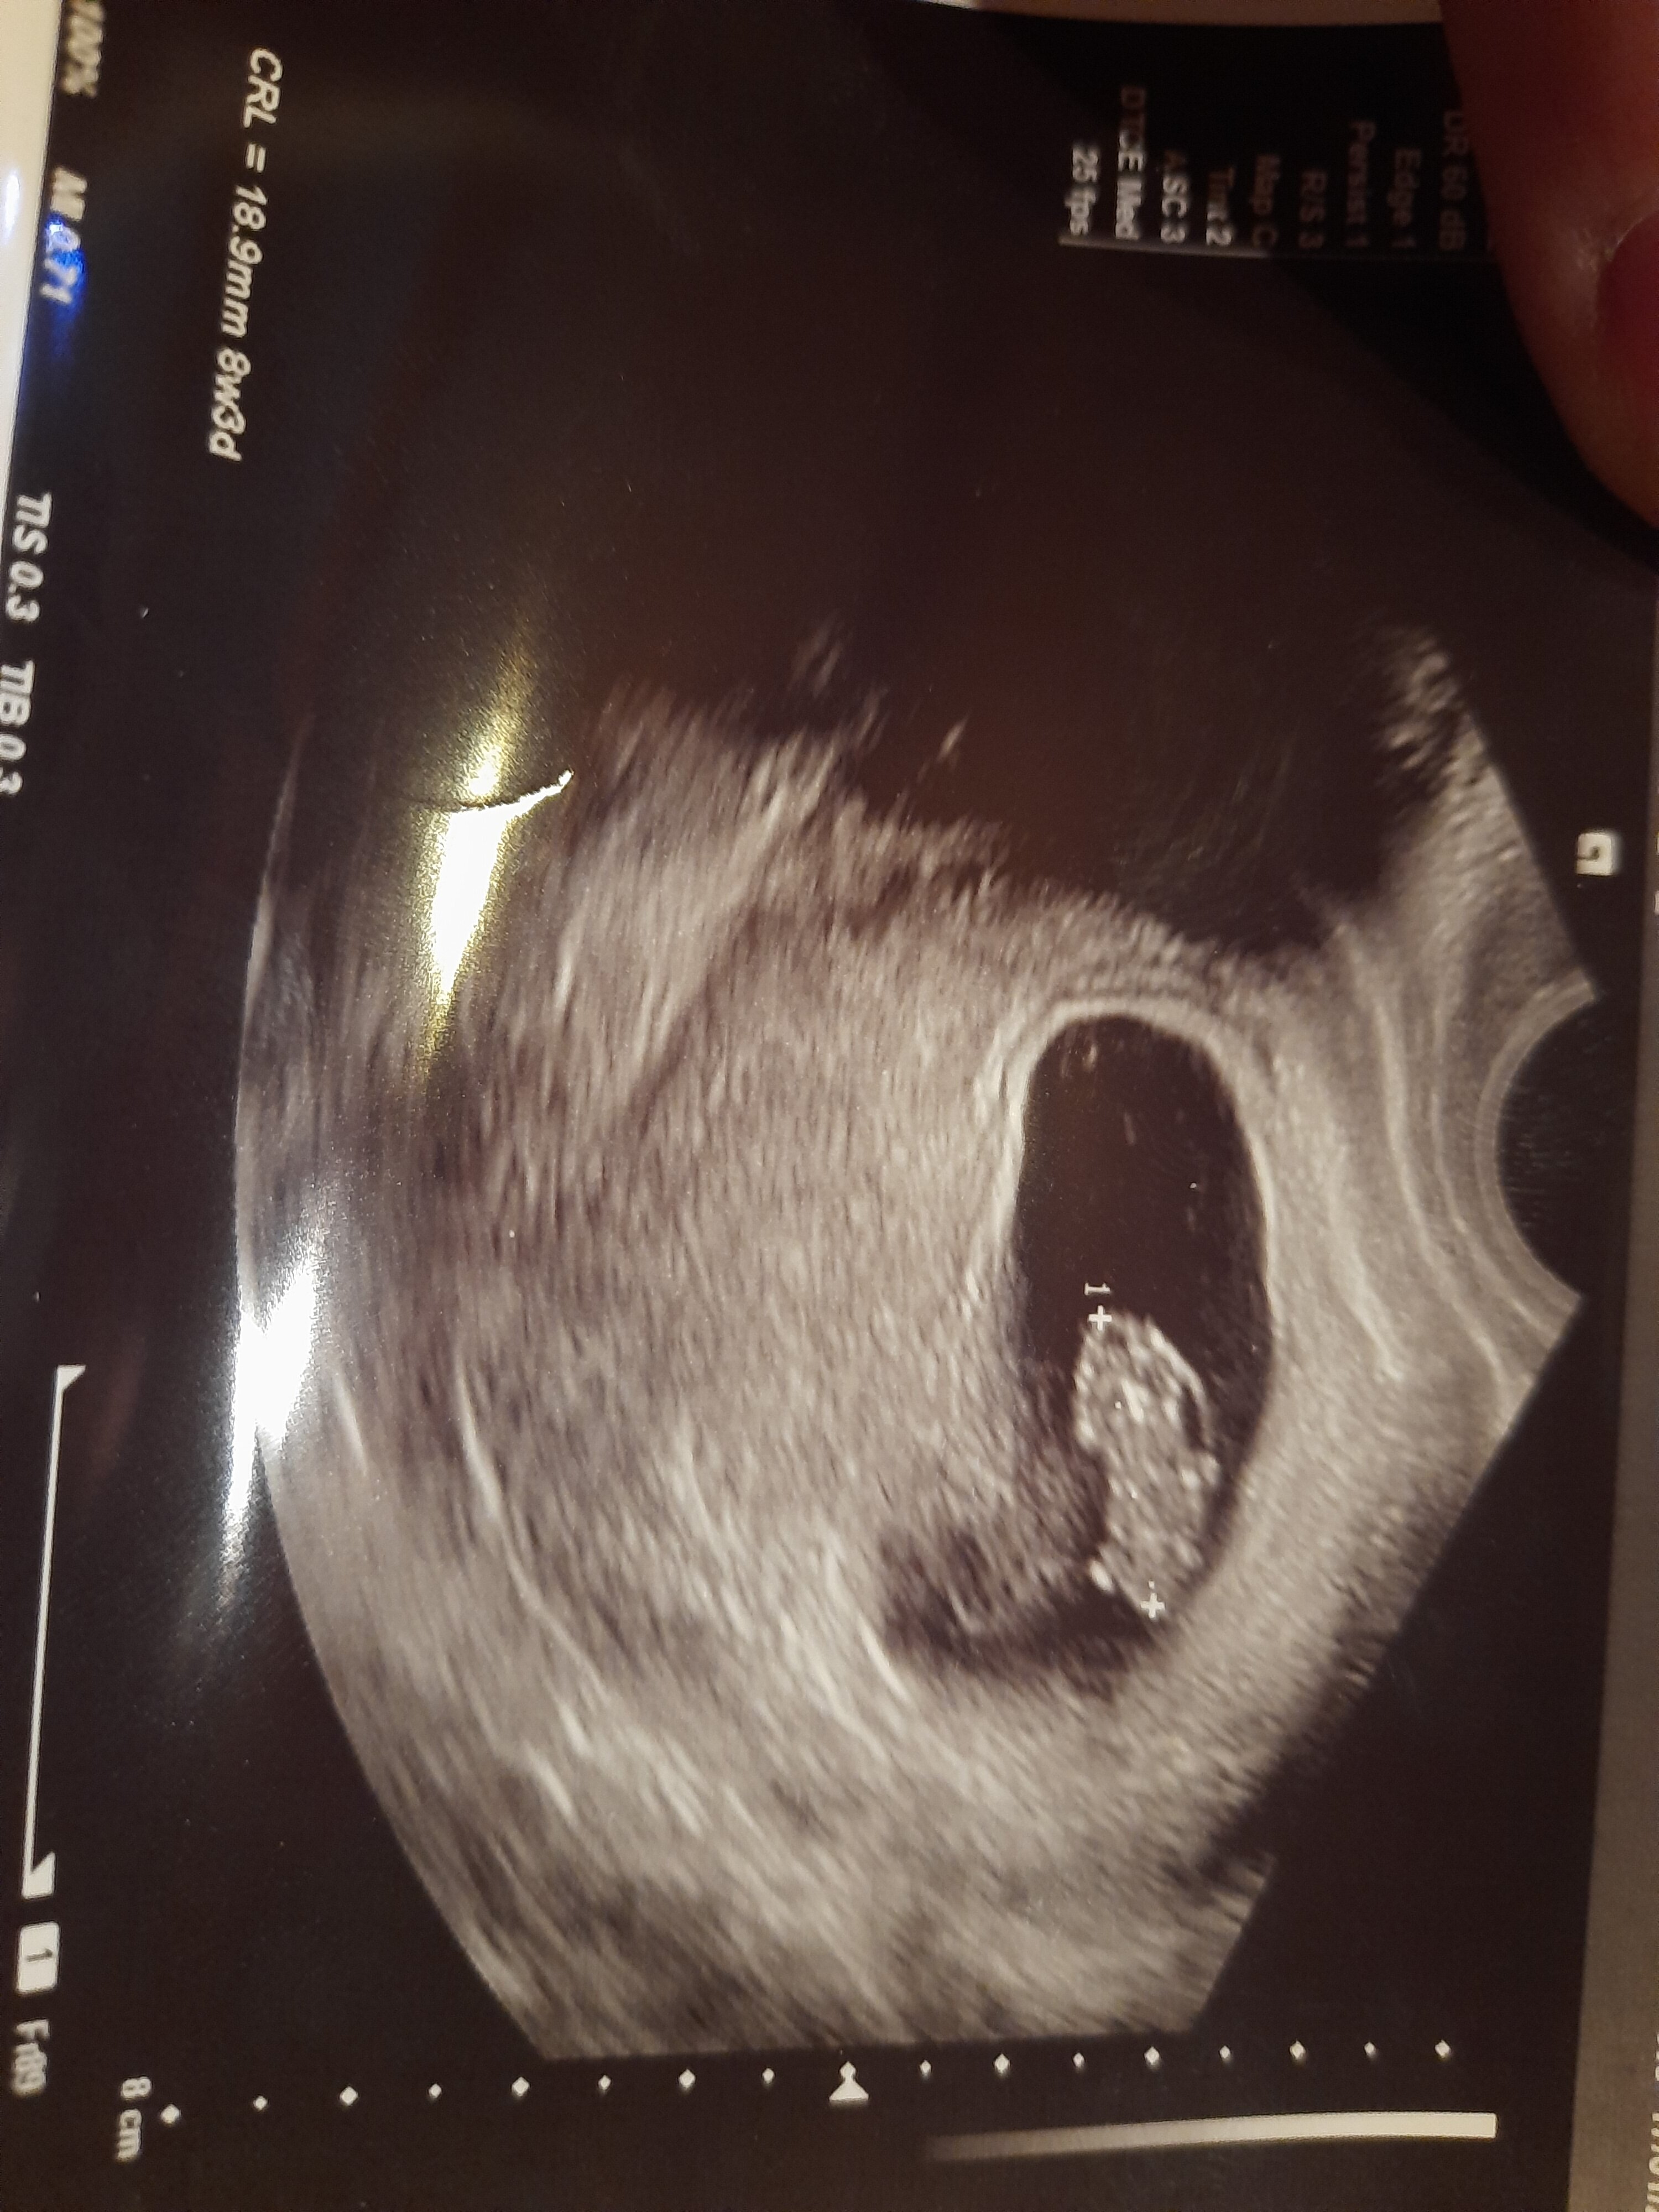

@kropka. Dostałaś jakieś zdjęcie z usg od lekarza? Czy na NFZ w ogóle dają takie zdjęcia? Chciałabym mieć aby móc pokazać przyszłemu tacie.👨🏻 zawsze czeka

Dostałam

Byłam na wizycie na Nfz. Lekarz pomierzyl, wszystko się zgadza, serce bije. Wyniki super. Tylko zwrócił uwagę, ze jest jakiś obrzęk. Wpisał mi na skierowaniu na badania prenatalne ' podejrzenie obrzęku zarodka' 🥺🥺 jestem załamana. Potem powiedział, że to może nic nie znaczyć I po prostu to zniknie jak zarodek będzie większy. Wszystko ma się okazać na prenatalnych.. jeszcze kazał mi zmienić luteine dopochwowa na duphaston.. ja wiem, że to młody lekarz, słaby sprzęt.. Ale może jest jakaś wada zarodka.. I teraz mam czekać 3 tygodnie...?

Znam sprawę jeśli chodzi o obrzęk .:duży jest ? Masz zdj ? Obrzęk może zrobić się jeśli byłaś chora jakaś infekcja wirusowa np